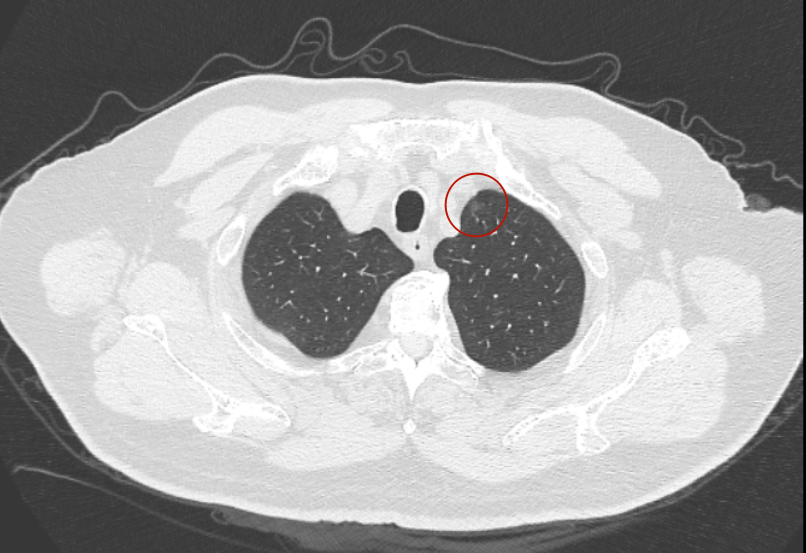

第三次问诊:2026.3

影像展示与分析:

再看2026年3月最近复查时不同层面病灶A的细节影像特征:

再看病灶B的2026年3月细节影像特征:

边缘位置也是较淡的磨玻璃成分。

上图是混合密度,轮廓较清,瘤肺边界欠清晰。

病灶A以及他处磨玻璃结节其实进展都是不明显的,略与2022年比,病灶A稍显明显点。病灶B开始时极淡,之前进展虽有但也甚微,直到2025年9月仍是磨玻璃成分为主,只是点状少许密度稍高成分。但在最近半年内却显然进展!若从影像上判断,基本上就得是浸润性腺癌了。那有几点:一是必不能再随访;二是大小来看仍是1A期;三是从快速进展来说,可能含有部分高危亚型,比如微乳头或实体型等;四是他处的磨玻璃结节以及病灶A显然不能用病灶B的转移来解释,仍考虑是多原发早期肺癌。

结友问能否先穿刺?我是这么考虑的:你这个病灶B一是位置深,且靠近附近的血管,不容易穿刺;二是从影像变化来看,基本上肯定是恶性的,不是100%,也是95%以上的概率。刚才我又在重建看冠状位与矢状位以及各次影像,目前混合密度的其实是后来者居上,原来刚开始是它比旁边的病灶密度淡的,但它的密度不是太纯,前次你自己也说似乎有点状偏实性成分。只是最近这半年进展特别快。这说明它的恶性程度较它边上原来就比较明显的那处恶性程度高,亚型中大概率有低分化的成分。所以从目前的影像来看,要尽快手术,而且切肺叶更为稳妥些。